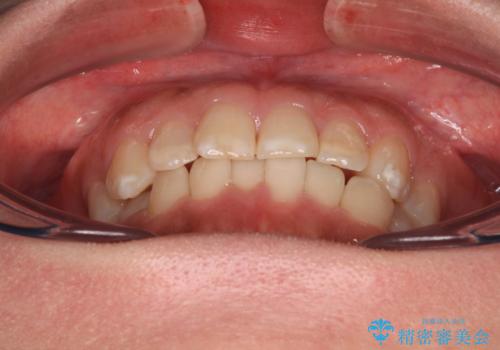

インビザライン・モデレートを用いて気になる前歯を短期間で矯正治療

- 8ヶ月

- 5-10回

インビザライン・モデレートは、製作できるアライナーの枚数に制限があるため、移動可能な量に限りがあるものの、インビザライン・ライトよりも枚数が多いため、幅広い症例に対応可能です。